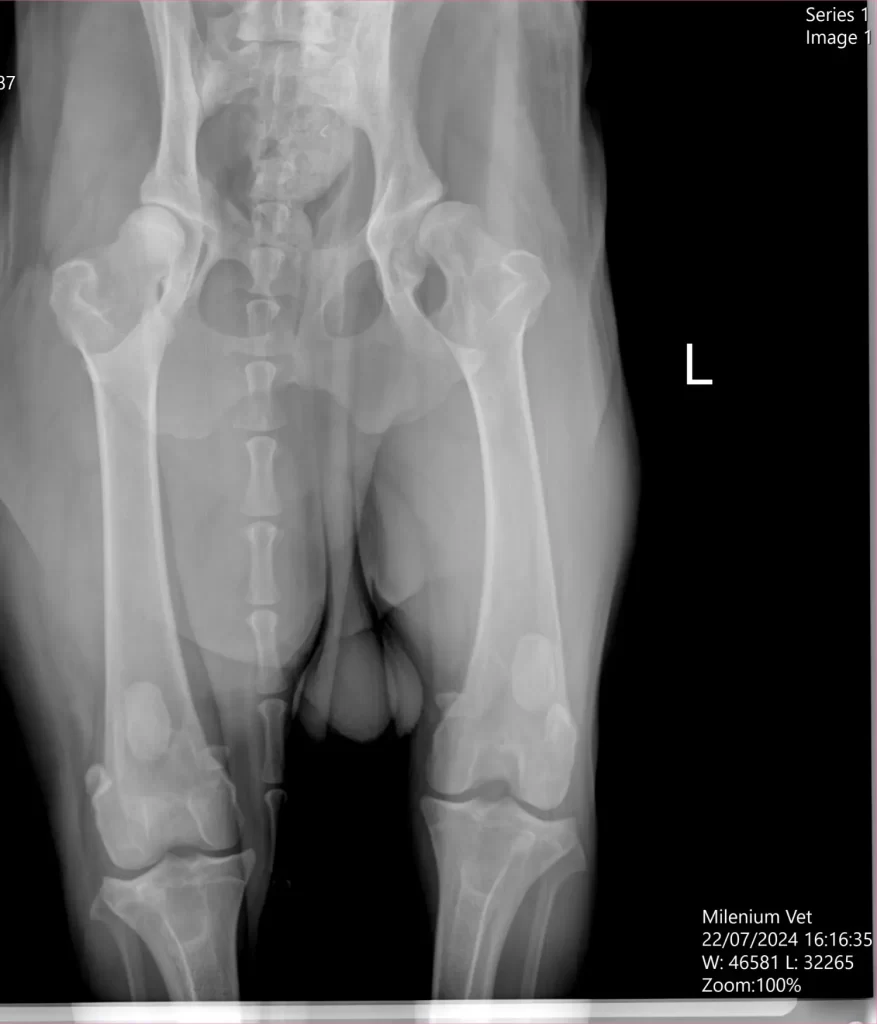

Upitan na koji način se displazija pasa dijagnostikuje, dr Panić naglašava da se dijagnostika displazije kukova i laktova obavlja kliničkim pregledom, ali pošto se ona smatra i skrivenom manom, a da bi se donela konačnu dijagnostiku displazije svakako je neophodno uraditi ortopedski pregled i RTG dijagnostika kao jedan od najpouzdanijih metoda u donošenju konačne dijagnoze. Znači za konačnu dijagnostiku bazira se na kliničkoj slici psa, ortopedskom pregledu i radiološkoj dijagnostici. Kada je reč o rasama pasa, dr Panić naglašava da se displazija može javiti kod svih rasa pasa, ali najčešće se manifestuje kod velikih i krupnih rasa poput nemačke doge, labradora, nemačkih ovčara, bernadnica, rotvajlera. Faktori koji dovode do displazije pored genetiku su i prekomerni rast, prekomerna težina, neizbalansirana ishrana, kao i prekomerno vežbanje, a koji mogu povećati genetsku predispoziciju.

Zato dr Panić naglašava da je veoma bitno da se vlasnik, ukoliko primeti neke od gore navedenih simptoma što pre javi svom veterinaru. Veterinar će na osnovu dijagnostike rtg snimka, proceniti o kom stepenu displazije se radi, da li je to neki blaži oblik ili teži stepen displazije. Shodno nalazu i dijagnostici veterinar će dati preporuku o daljem toku lečenja. Kod blažih oblika se često sprovodi konzervativno lečenje (medikamentima), dok je kod ozbiljnijih displazija potrebno nekada pristupiti I hirurškom zahvatu.